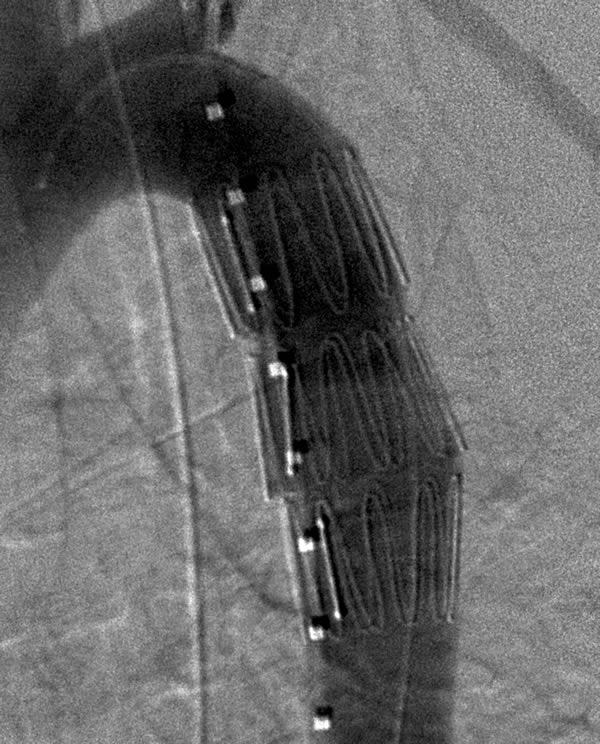

Figure 1: Left anterior oblique aortogram obtained with measuring pigtail catheter demonstrating aortic arch anatomy and location of aortic transection.

The patients are usually intubated as part of their initial resuscitation and have general anesthesia provided by an anesthesiology team for the procedure. In our institution, the procedure is performed in a conventional angiographic suite using ceiling-mounted Siemens Axiom ARTIS equipment (Erlangen, Germany). Patients are positioned supine with both groins prepped and draped. A 5-F graduated measuring pigtail catheter (Angiodynamics, Queensbury, NY) is inserted percutaneously via the left common femoral artery and a left anterior oblique arch aortogram is obtained to confirm arch anatomy and the location of the injury (Figure 1). Additional views, including selective vertebral artery injections, are performed as necessary.